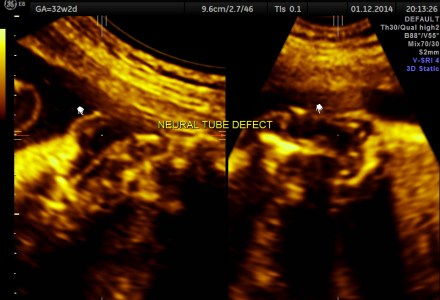

NEURAL TUBE DEFECT